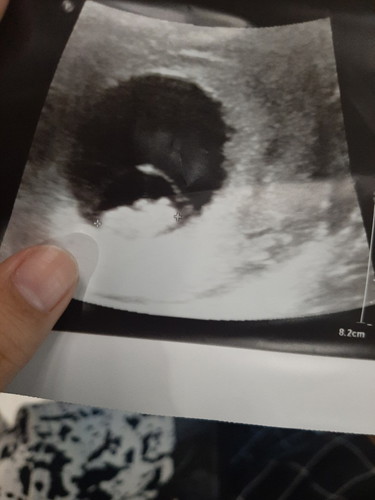

8wแม่ๆเป็นยังไงกันบ้าง

ช่วยดูหน่อยคืออะไร เป็นตัวรึยัง ☺️

ตัวอ่อนจ๊ะ จะเริ่มเห็นเป็นทารกชัดๆตอนประมาณ 12 วีคจ้า